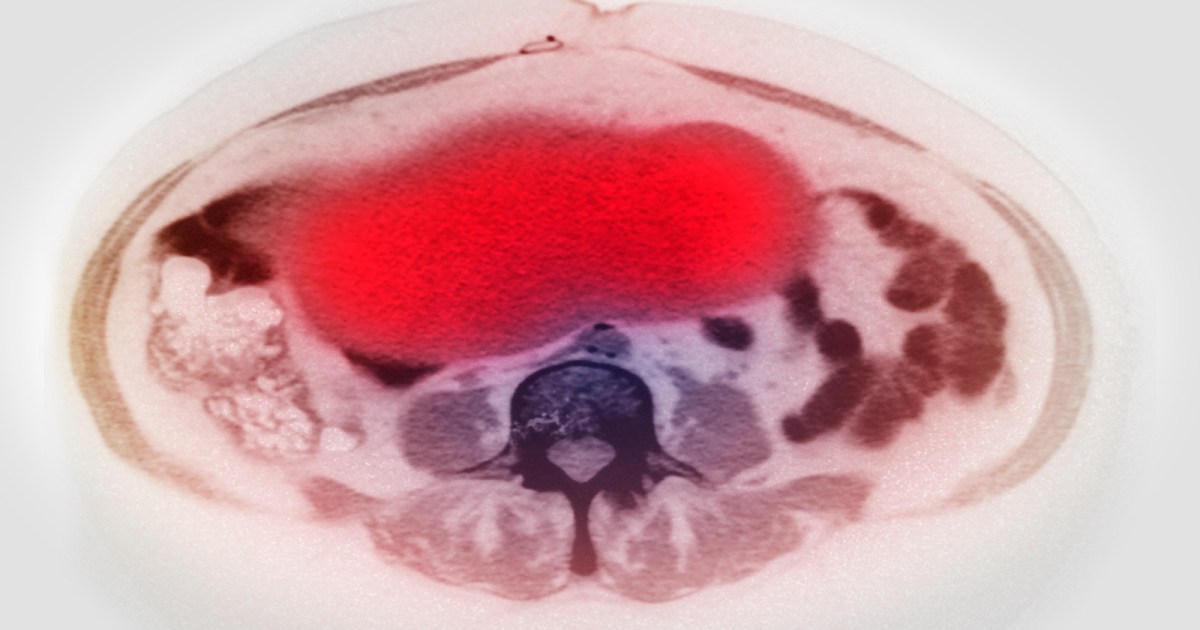

• Constant swelling or swelling in the abdomen.

• Constant pain in the stomach, back or pelvis.

“Abonet De” pointed out that the first step to treat ovarian cancer is surgery to remove the largest possible tumor, perhaps both ovaries, fallopian tubes, uterus and parts of the neighboring organs.